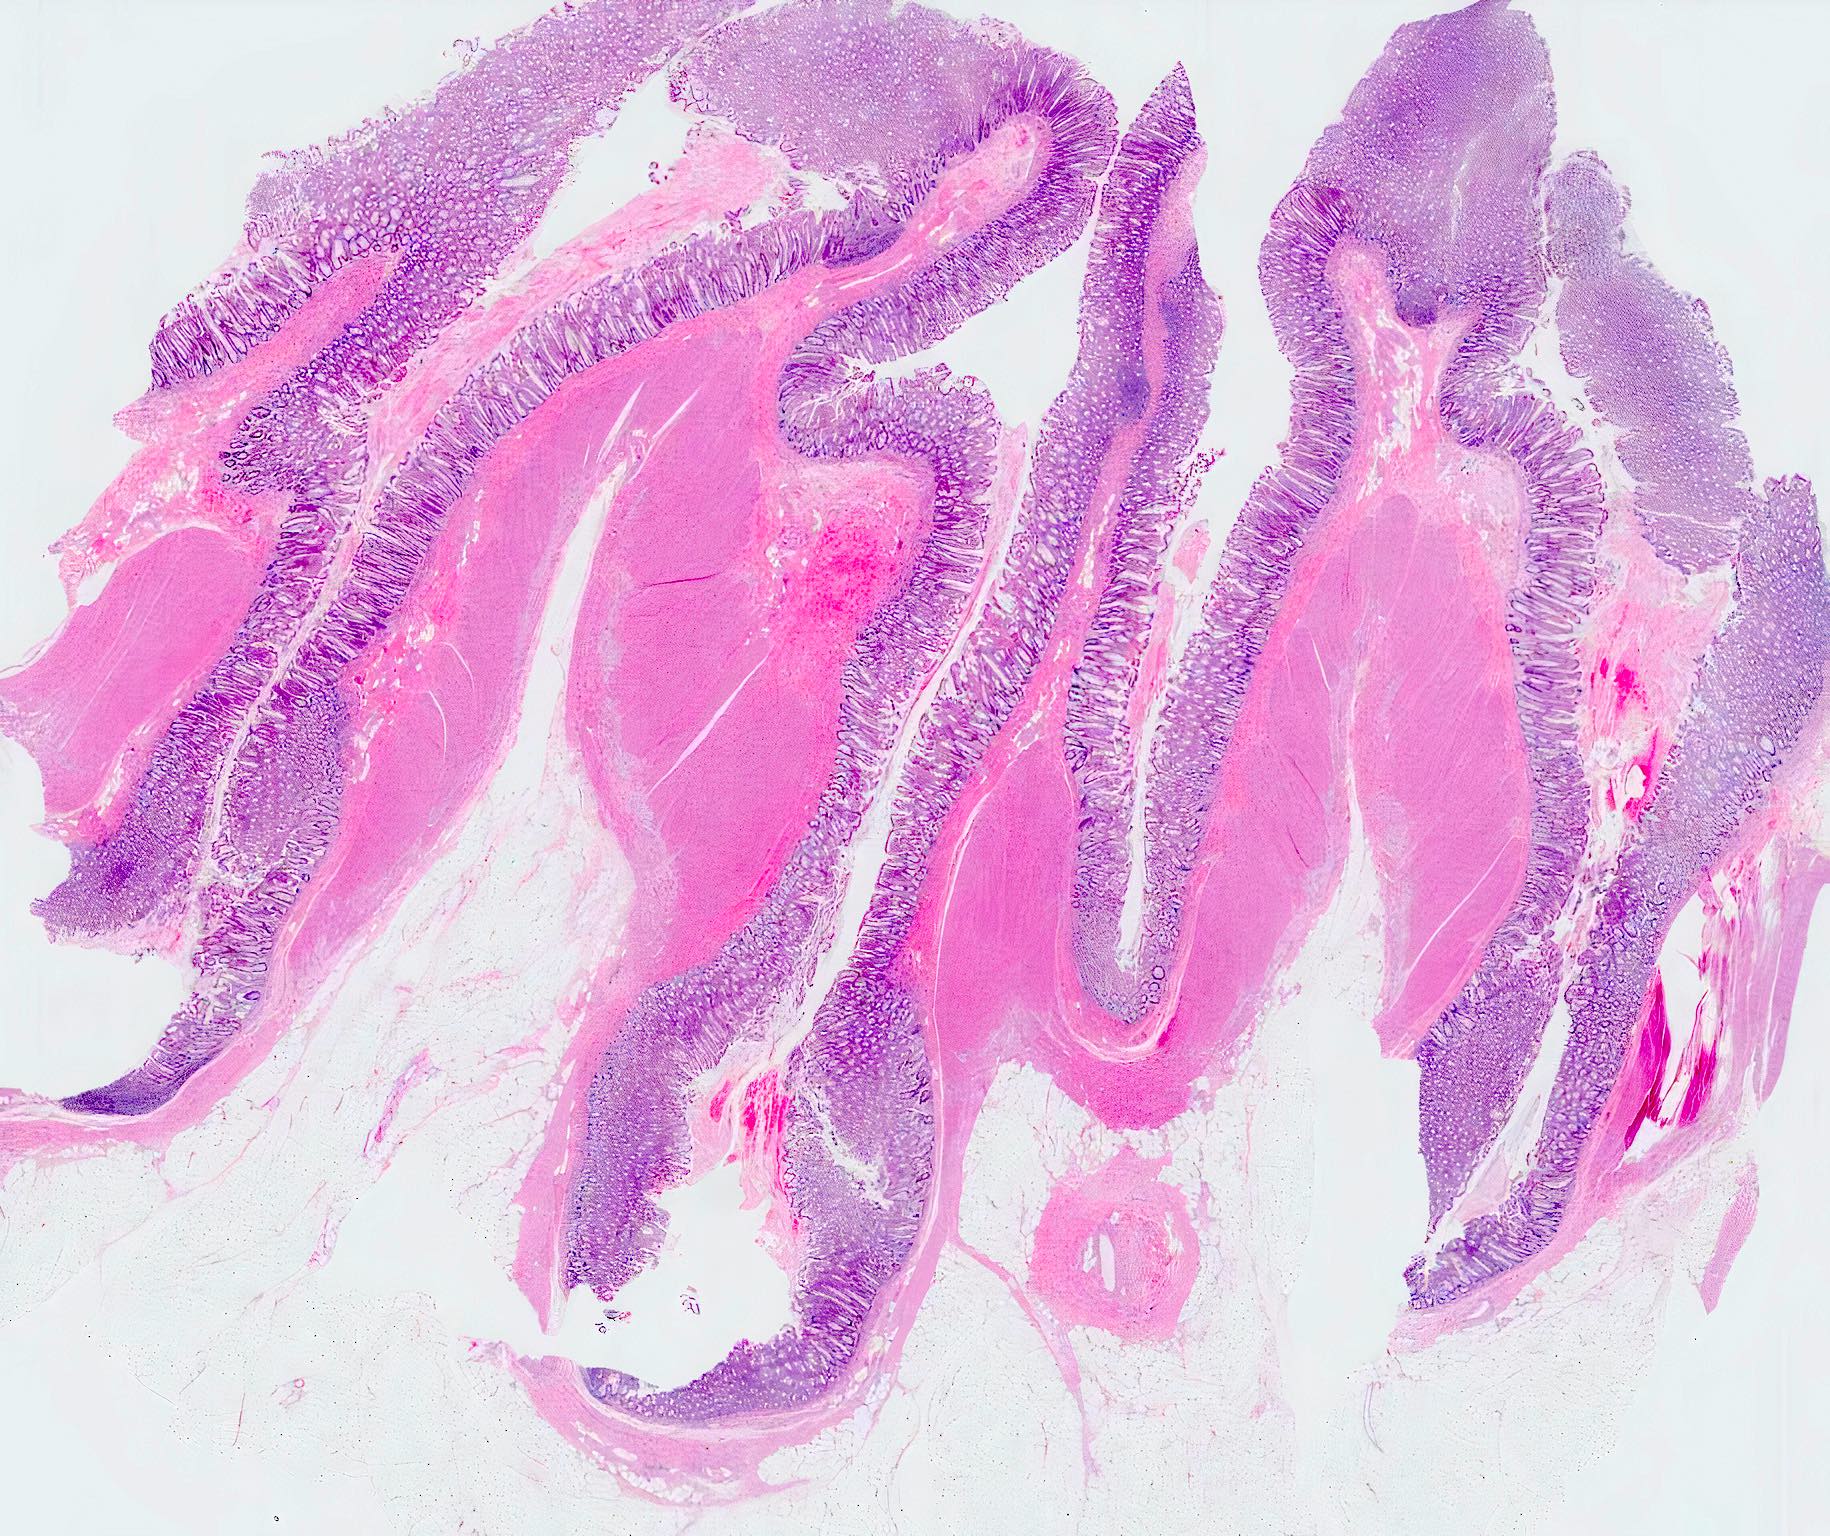

Microscopic (histologic) description

- Mucosa may be normal to markedly abnormal

- Expansion of lamina propria by lymphoplasmacytic infiltrate (more prominent in basal half)

- Lymphoglandular complexes, mucin depletion, focal Paneth cell metaplasia (in chronic cases) may be seen (J Clin Gastroenterol 2004;38:S11)

- Muscularis mucosa extends towards surface between elongated crypts

- Shortening of the affected bowel and hypertrophy of circular muscle layer (myochosis) leads to exaggerated mucosal folds (Am J Surg Pathol 1991;15:871)

- Some cases can show lamina propria fibrosis, crypt elongation on the tips of prominent mucosal folds, like mucosal prolapse syndrome in rectum and anus (J Clin Gastroenterol 2008;42:1137)

- Hemosiderin deposition in submucosa may be seen (StatPearls: Diverticulosis [Accessed 21 April 2022])

- Can mimic inflammatory bowel disease

- Hyperplasia of lymphoid aggregates is one of the earliest signs of diverticulitis

- Cryptitis, crypt abscesses, peridiverticular abscess and fistulas may be superimposed on this background in acute diverticulitis

- Tracking abscesses can spread longitudinally or circumferentially and can cause diverticular colitis

- Persistent localized inflammation can lead to phlegmon which is a thickened, firm segment of bowel wall that can lead to strictures and acute or subacute large bowel obstruction (Best Pract Res Clin Gastroenterol 2002;16:543)

Microscopic (histologic) images

Contributed by Bindu Challa, M.D. and Martha M. Yearsley, M.D.